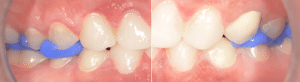

Elle se rend compte que pour avoir ce sourire, il faut surélever en postérieur. La patiente valide le plan de traitement. Avec le mock-up en bouche, on enregistre avec de la résine d’occlusion (ici LuxaBite, DMG) l’espace d’inocclusion postérieur (Fig.5) en réalisant deux clés (une droite et une gauche). Cela permet d’avoir une stabilité dans le repositionnement des arcades lors des prochains enregistrements numériques.

Fig.5 : Enregistrement de l’espace d’inocclusion postérieur.

On réalise une nouvelle empreinte optique (Fig.6a, b) avec le mock-up antérieur en bouche. Elle devient notre empreinte de référence de DV tout au long du traitement. On s’aperçoit bien qu’à cette étape, seuls les secteurs antérieurs sont en occlusion.

Fig.6a, b : Empreinte optique.

Fig.6b.

Astuce

Afin d’enregistrer l’occlusion numériquement alors qu’il n’y a pas de calage postérieur, on utilise les clés précédemment réalisées. On met la clé droite et on enregistre « l’occlusion » à gauche. Puis on met la clé gauche et on enregistre « l’occlusion » à droite. Enfin, on positionne les deux clés et on enregistre l’occlusion en antérieur.